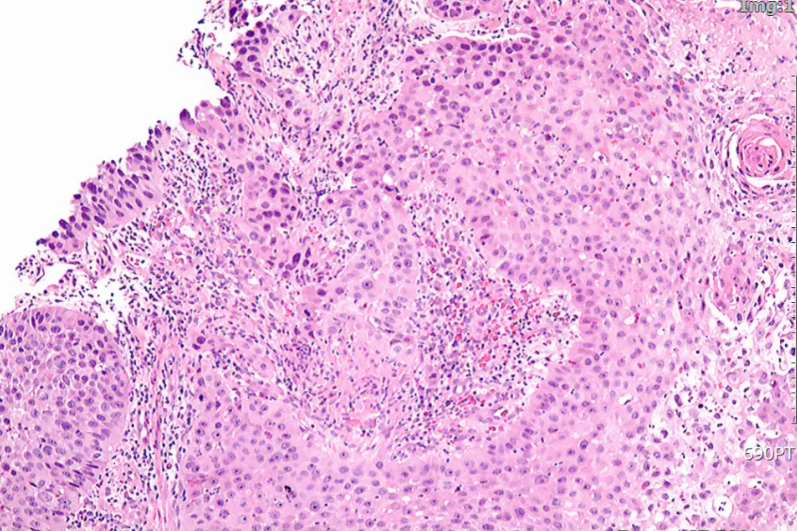

图1 胃镜检查

图像(2019年11月)

图2 病理检查

图像

现病史:患者于2019年9月无明显诱因出现进食吞咽困难。2019年11月,电子胃镜

示:距门齿30cm处可见一不规则肿物,病灶占据管腔近1周,伴管腔狭窄,无法通过胃镜。病理示:食管中分化鳞状细胞癌。